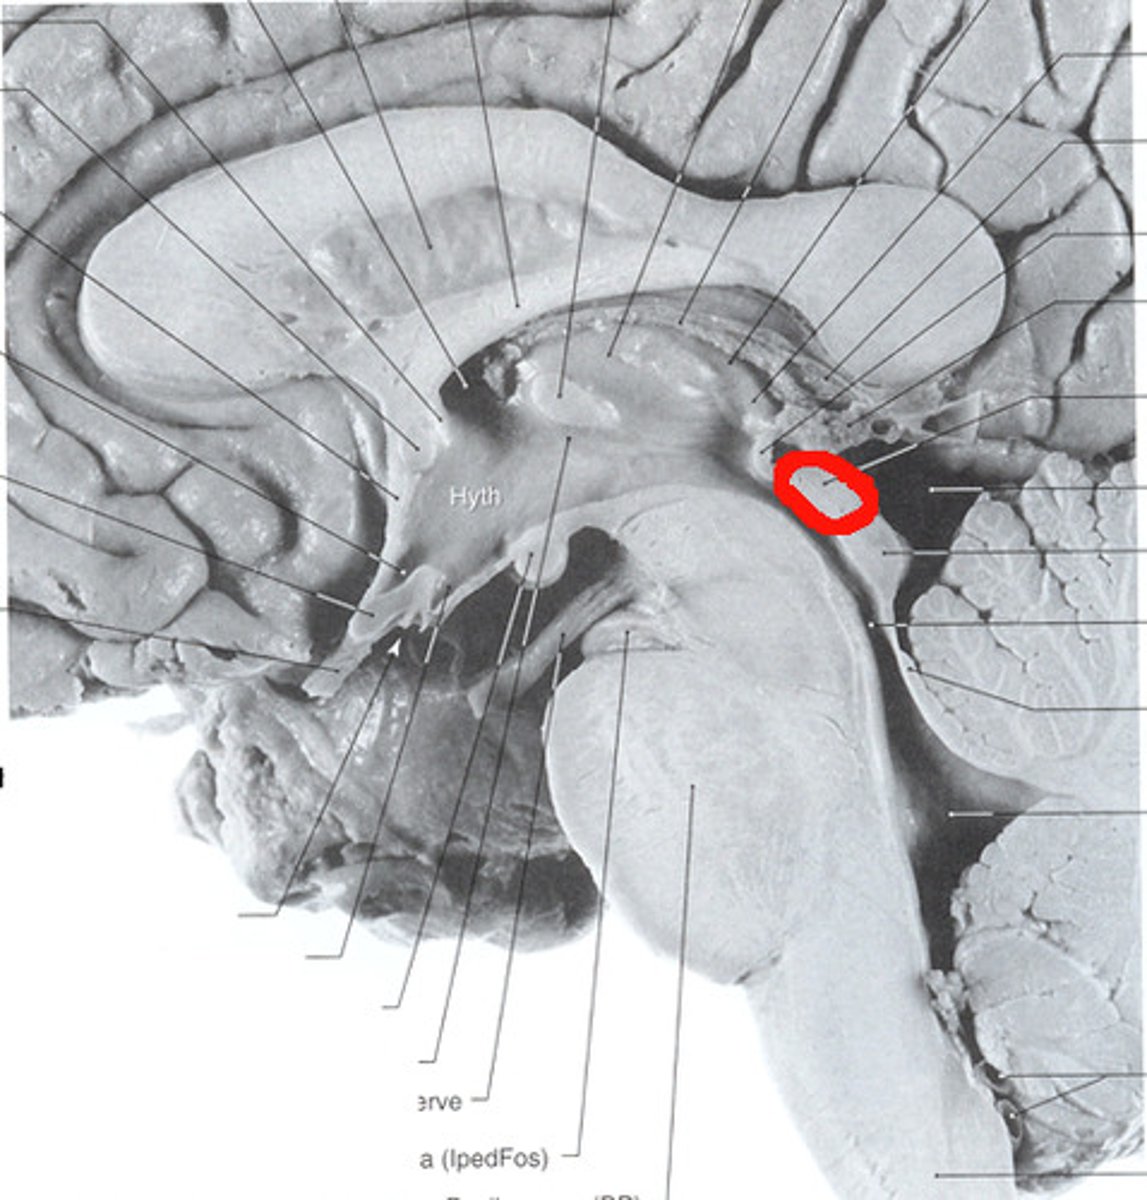

superior colliculus

where>what; integrates from multiple senses to figure out where things are in space; coordinating and planning eye movement

optic chiasm

the point in the brain where the visual field information from each eye "crosses over" to the appropriate side of the brain for processing